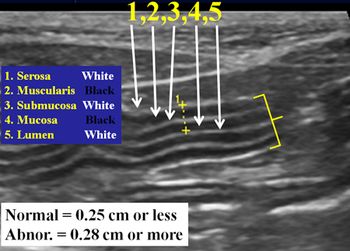

What to look for when evaluating cats for small bowel disease as a cause of chronic vomiting.

Most chronic vomiting and chronic diarrhea in cats originate in the small bowel

Most chronic vomiting and chronic diarrhea in cats originate in the small bowel.